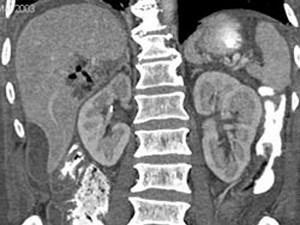

问题 男,44岁,发热、右上腹痛、压痛,右下肺呼吸音低,影像检查如图,最佳诊断是 ( )

选项 A、肝硬化腹水 B、肝癌 C、膈下脓肿 D、肝包膜下出血 E、腹腔积液

答案 C